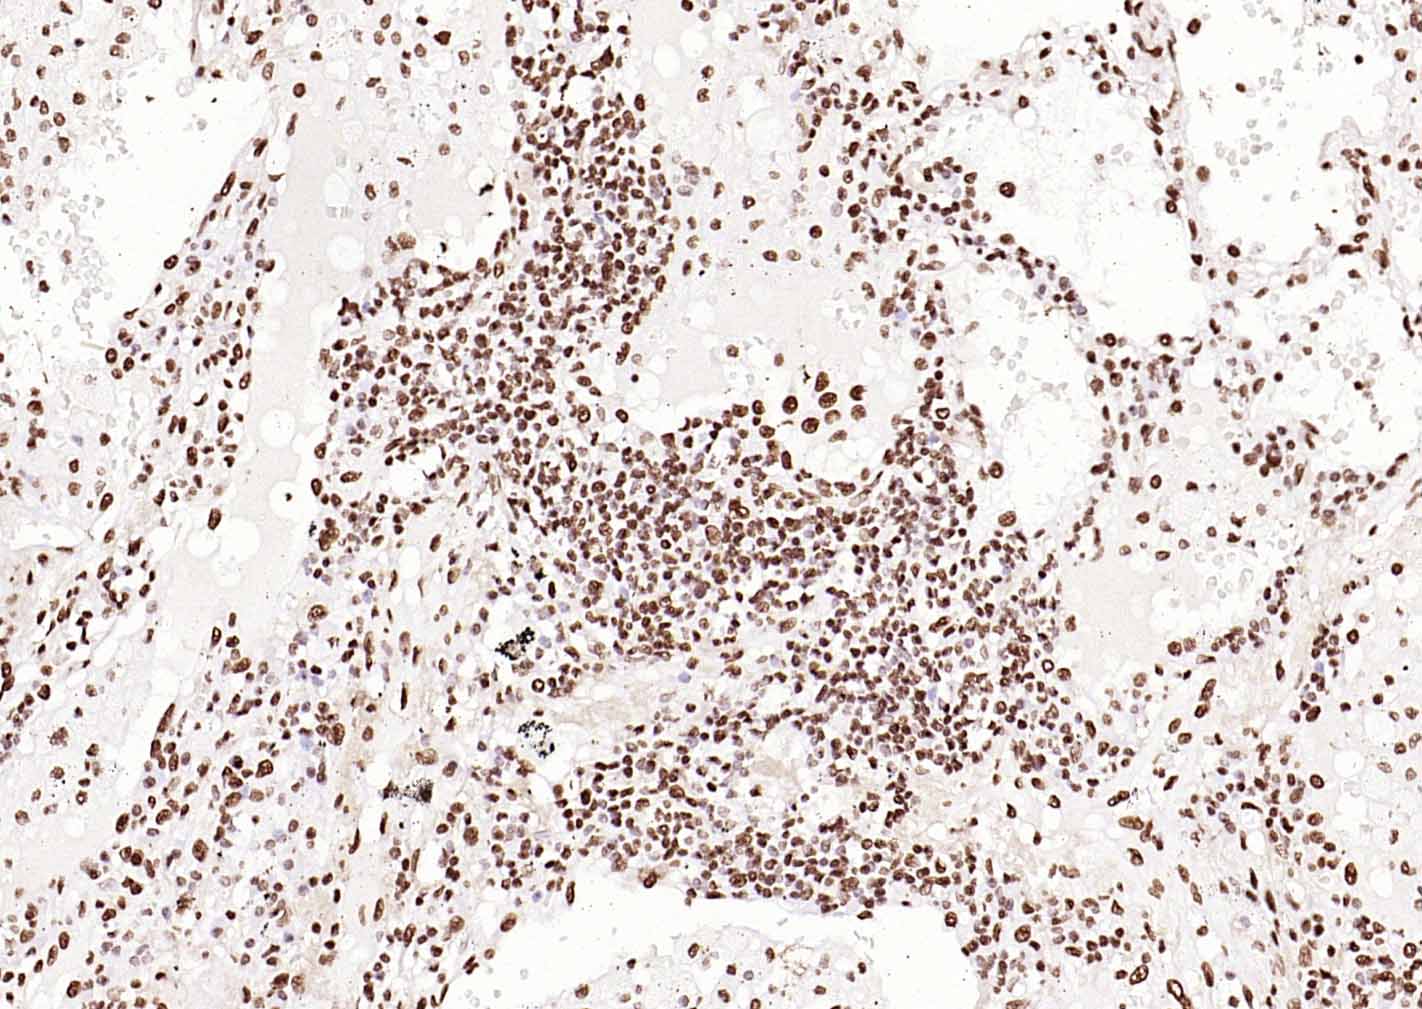

Paraformaldehyde-fixed, paraffin embedded (human colon carcinoma); Antigen retrieval by boiling in sodium citrate buffer (pH6.0) for 15min; Block endogenous peroxidase by 3% hydrogen peroxide for 20 minutes; Blocking buffer (normal goat serum) at 37°C for 30min; Incubation with (ERCC1 ) Monoclonal Antibody, Unconjugated (bsm-60230R) at 1:200 overnight at 4°C, followed by operating according to SP Kit(Rabbit) (sp-0023)instructionsand DAB staining.